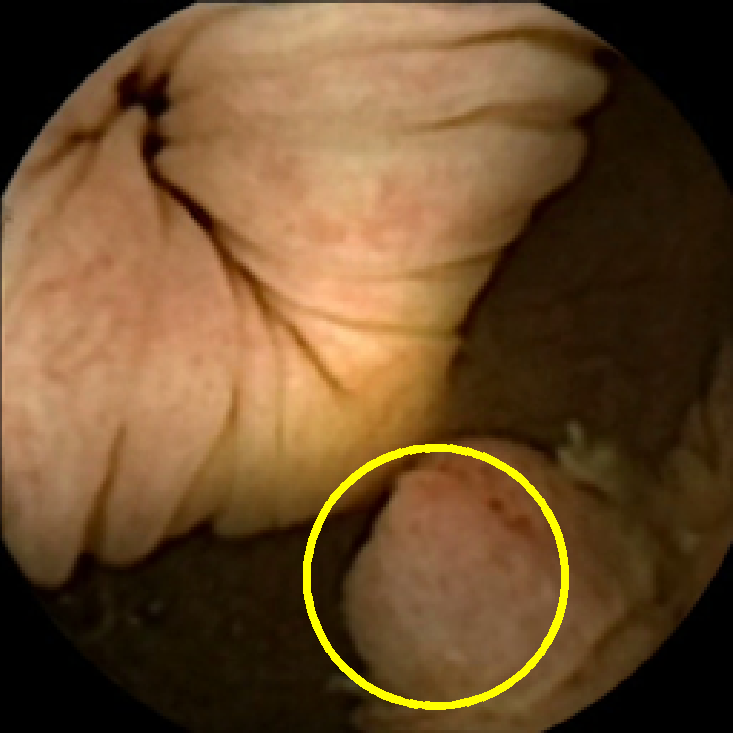

We illustrate the above considerations in Figure 4, where we compare the ellipses of inertia for a polyp frame and two frames with pronounced mucosal folds. The ellipses we plot are

| (20) |

where . The scaling term in front of is chosen so that the area of the ellipse of inertia is the same as the size of the corresponding feature.

As expected, we observe that the ellipses corresponding to mucosal folds (feature 2 in the second row and features 2 and 3 in the third row of Figure 4) are indeed much more stretched out than the ellipse corresponding to a polyp (feature 1 in the first row of Figure 4). Stretched ellipses imply higher eccentricity, thus we impose the following criterion

| (21) |

with some threshold to select moderately stretched features that are more likely to correspond to polyps.